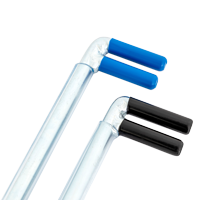

Kids open knee brace AM-DOSK-O/1R is an excellent solution when knee immobilization and stabilization is needed. The brace is equipped with innovative drop lock providing range of motion adjustment in every 15°. Regarding to needs, you can limit the joint motion or immobilize it. Our kids knee brace is approved and certificated by famous institutes, conforming its quality and safety.

Our kids knee brace AM-DOSK-O/1R stabilizes the knee in frontal plane and supports the knee even in case of severe instability. In case of strain or sprain knee, our drop lock 1R orthodesign provides knee immobilization in 0°. Then, when the joint motion is bigger, our drop lock allows to adjust required degree of knee flexion in every 15°. Internal cotton layer is soft and skin friendly. The fabric keeps the skin dry and promotes healing reducing the swelling and bruising.